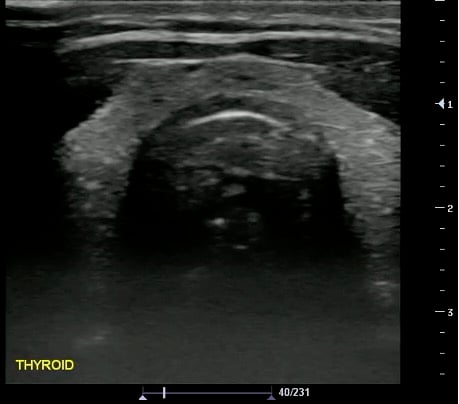

- Normal Thyroid Isthmus and Bilateral Lobes

- Figure 31 and 32. Thyroid

- Normal findings

- Homogeneous ground-glass appearance

- Hyperechoic relative to adjacent muscles

Video 21. Normal Thyroid - Measurements:

- Obtained in 3 dimensions (anteroposterior, transverse, and longitudinal)

- Nodule > 10 mm concerning for malignancy (controversial; not the only criteria)

- Additional measurements: Isthmus thickness (Transverse > 5mm abnormal), Lobe volume (Width x Length x Depth x 0.5)